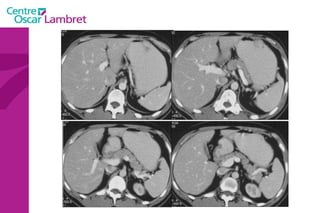

Le Foie

Le sang quitte le foie par trois veines sus-hépatiques principales (droite, médiane et gauche) et des veines accessoires qui drainent le segment 1 (ou lobe de Spiegel. Les veines sus-hépatiques  principales délimitent 4 secteurs composés chacun de 1 à 2 segments :  latéral gauche (segments 2 et 3), paramédian gauche (segment 4), paramédian droit (segments 5 et 8)  latéral (ou postérieur) droit (segments 6 et 7) Elles se jettent dans la veine cave inférieure. Le Foie : 8 segments